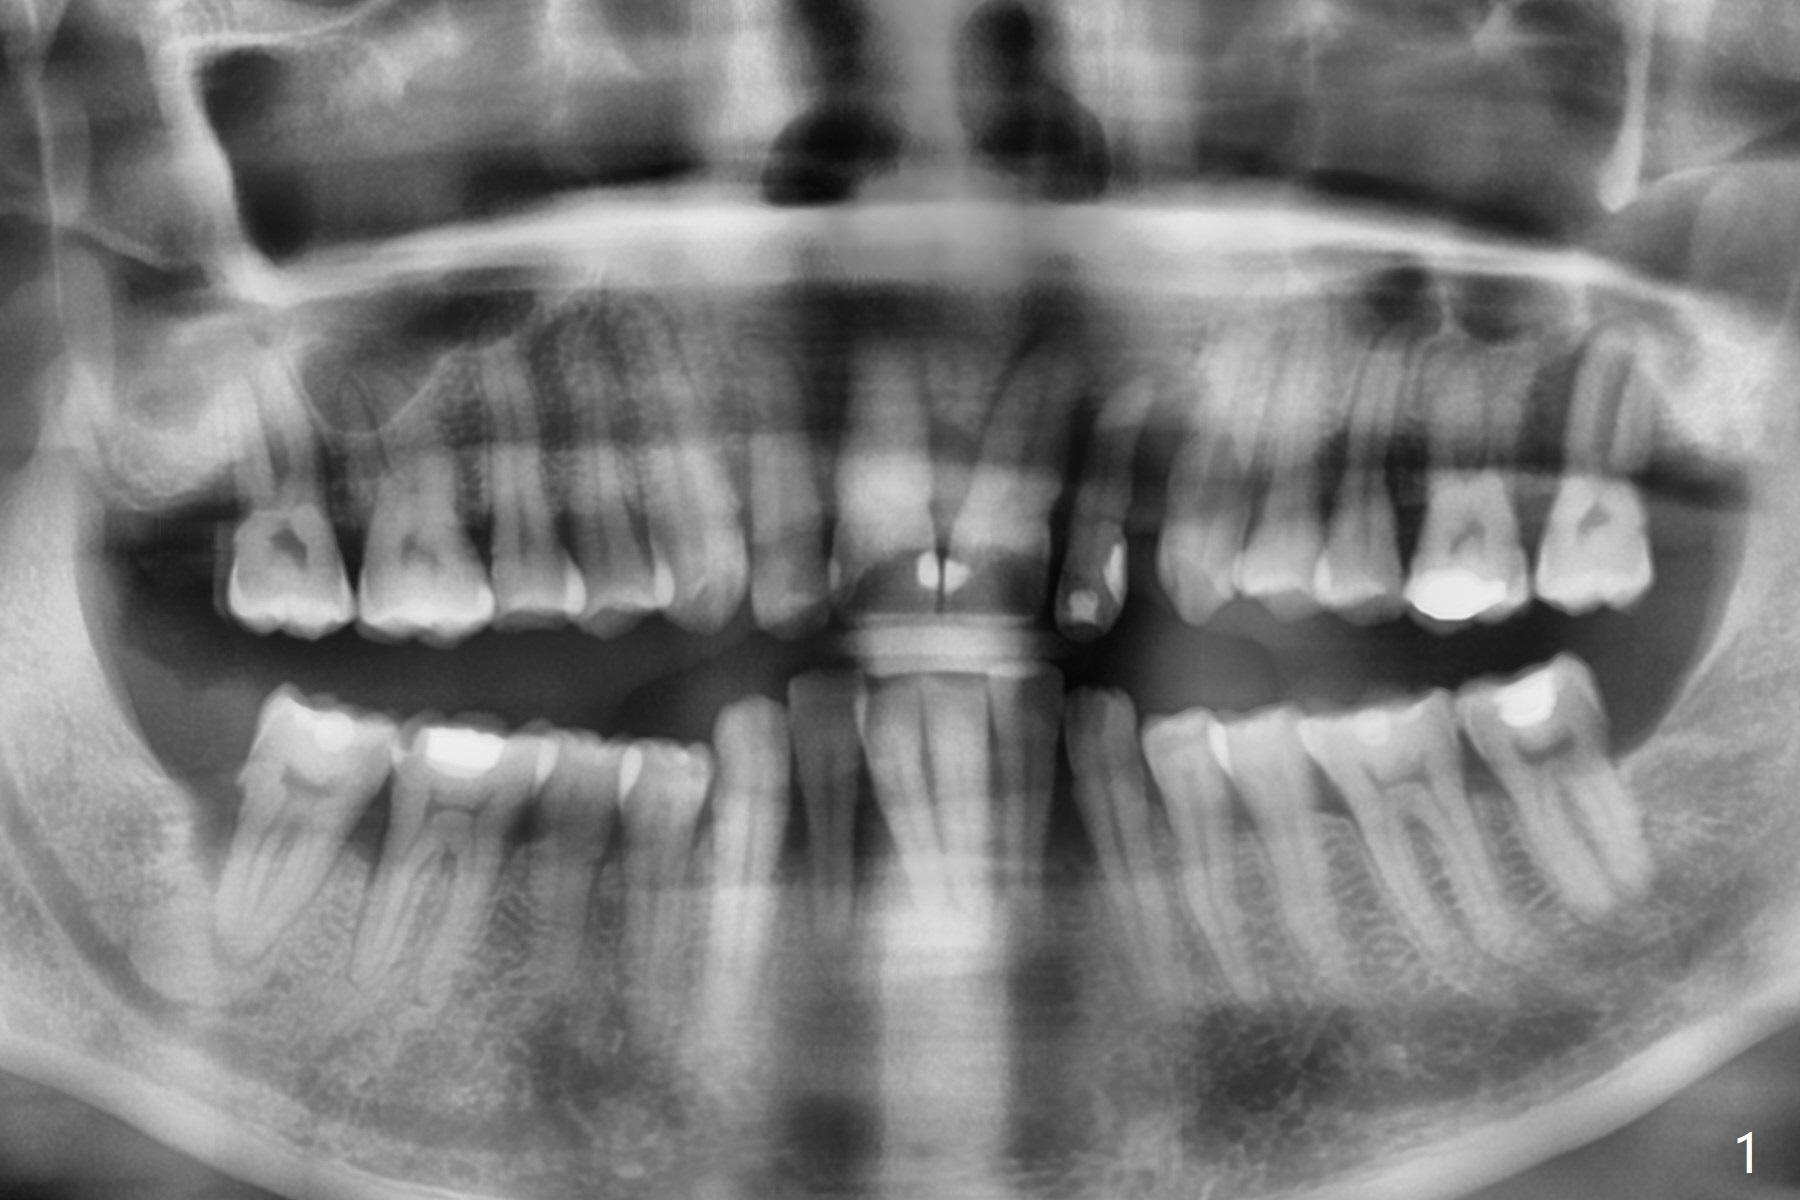

A 44-year-old man with generalized periodontitis (Fig.1) will return to clinic for #10 extraction (Fig.2) prior to brain tumor removal. Immediate implant (Fig.3) or not, sticky bone will be placed on the root surface of the neighboring teeth (Fig.4 red circles) after SRP. Place PRF membrane as early as possible, e.g, buccal, to avoid waste.